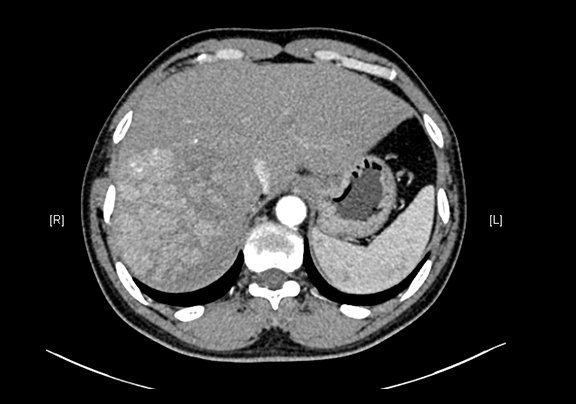

现病史:患者20余天前查体,行腹部超声检查时发现:肝右叶低回声结节,大小约5.8*4.7cm,无腹痛、腹胀,无腰背部放散痛、皮肤巩膜无黄染,无寒战、高热,无咳嗽、咳痰、胸闷、气短,无恶心、呕吐,无腹泻、血便,无尿频、尿急、尿痛、血尿。上腹部动态三维成像(增强)CT检查示,肝右后叶上段占位性病变,肿瘤性病变。

下腹部增强CT示:肝右后叶上段占位性病变,肿瘤性病变,考虑肝癌合并出血可能性大,肝多发小囊肿

术前CT检查:

动脉期

静脉期

平衡期